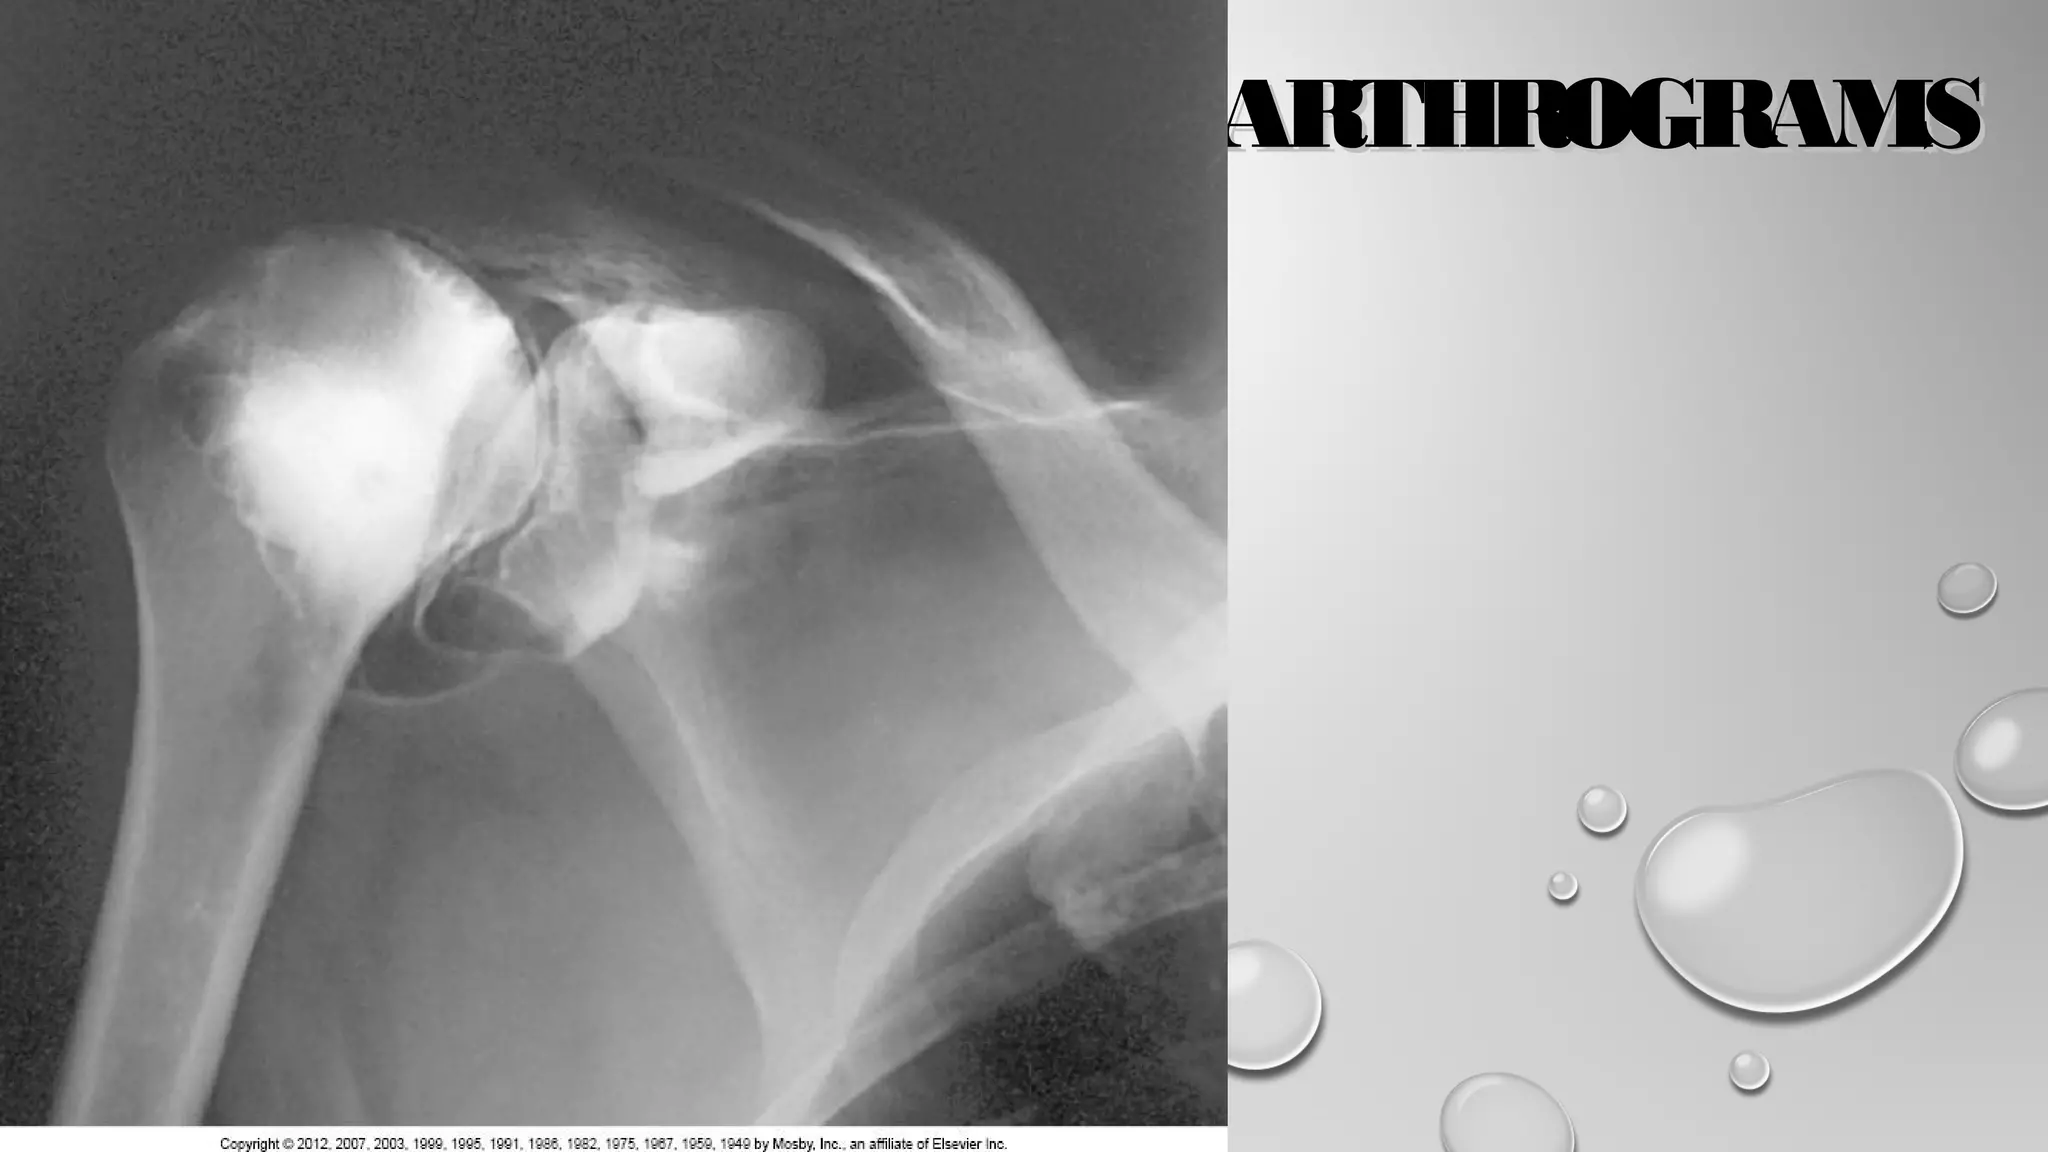

SHOULDERSHOULDER

PERFORMED TO EVALUATEPERFORMED TO EVALUATE

PARTIAL OR COMPLETEPARTIAL OR COMPLETE

TEARS IN ROTATOR CUFF ORTEARS IN ROTATOR CUFF OR

GLENOID LABRUMGLENOID LABRUM

PERSISTENT PAIN ORPERSISTENT PAIN OR

WEAKNESSWEAKNESS

FROZEN SHOULDERFROZEN SHOULDER

SINGLE OR DOUBLE-CONTRASTSINGLE OR DOUBLE-CONTRAST

TECHNIQUES MAY BE USEDTECHNIQUES MAY BE USED

SINGLE USES 0 TO 12 ML OFSINGLE USES 0 TO 12 ML OF

POSITIVE AGENTPOSITIVE AGENT

DOUBLE USES 2 TO 4 ML OFDOUBLE USES 2 TO 4 ML OF

POSITIVE AND 10 TO 12 MLPOSITIVE AND 10 TO 12 ML

OF AIROF AIR

• COMMON PROJECTIONSCOMMON PROJECTIONS

• AP IN INTERNAL AND EXTERNAL ROTATIONAP IN INTERNAL AND EXTERNAL ROTATION

• AP OBLIQUE, 30-DEGREE OBLIQUE POSITIONAP OBLIQUE, 30-DEGREE OBLIQUE POSITION

• AXILLARYAXILLARY

• TANGENTIALTANGENTIAL

• CT AND MRI OFTEN USED IN CONJUNCTION WITH SHOULDERCT AND MRI OFTEN USED IN CONJUNCTION WITH SHOULDER

ARTHROGRAMSARTHROGRAMS